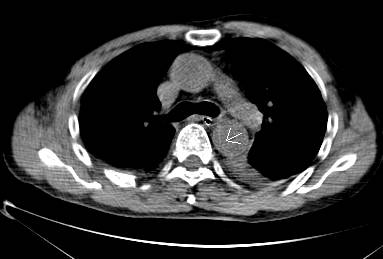

病例六

平扫CT提示降主动脉内膜片影(白箭头所示),CTA显示为B型主动脉夹层。

图12-13